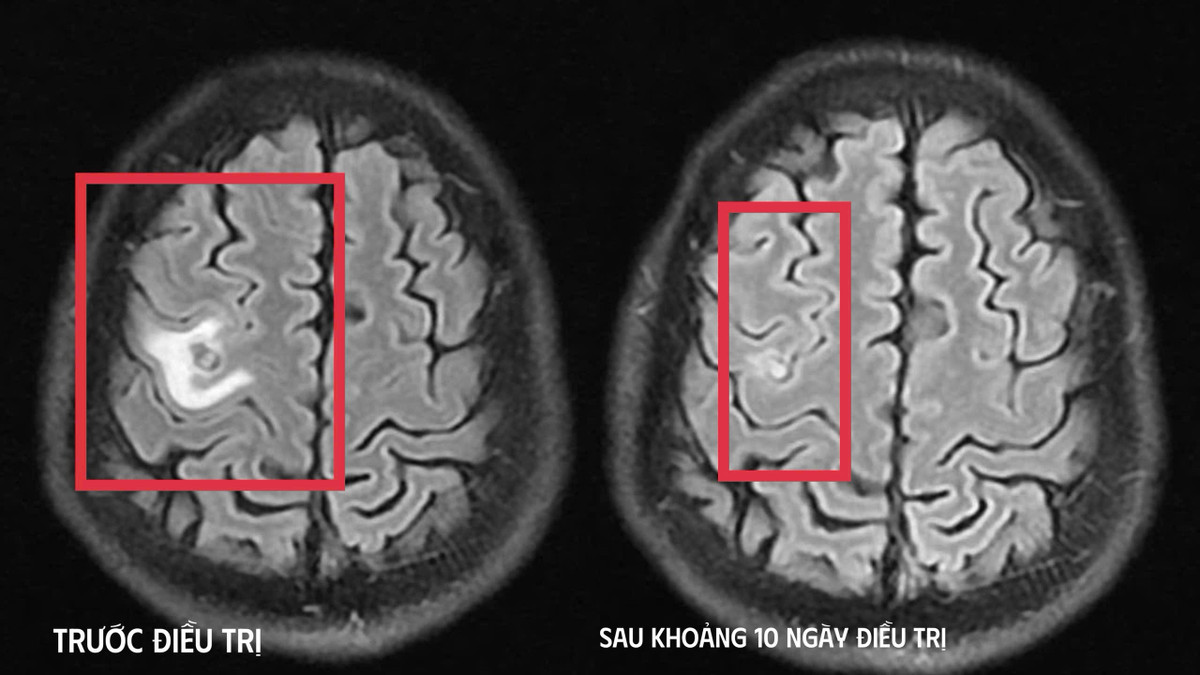

Bệnh nhân được chụp cộng hưởng từ (MRI) sọ não, phát hiện tổn thương dạng nang nhỏ tại thùy trán trái, kích thước khoảng 11 x 7 mm, xung quanh có phù não nhẹ. Hình ảnh này hướng nhiều đến tổn thương do ký sinh trùng hơn là u não nguyên phát.

Hình ảnh ổ sán não trước và sau điều trị - Ảnh BVCC

Sau khi xác định nguyên nhân, bệnh nhân được điều trị nội khoa theo phác đồ, kết hợp kiểm soát triệu chứng và theo dõi sát diễn biến thần kinh. Sau khoảng 10 ngày điều trị nội trú, tình trạng bệnh nhân cải thiện rõ rệt, hết tê tay, không còn xuất hiện cơn co giật, không đau đầu hay chóng mặt, toàn trạng ổn định. Người bệnh được cho ra viện và tiếp tục điều trị ngoại trú đủ liệu trình kéo dài 4 tuần.

Khi tái khám gần một tháng sau, kết quả chụp cộng hưởng từ cho thấy tổn thương não thu nhỏ (cụ thể hình dạng nang) rõ rệt, phù não giảm, không còn dấu hiệu tiến triển, đáp ứng điều trị tốt. Bệnh nhân tiếp tục được chỉ định thêm một đợt thuốc củng cố và theo dõi lâu dài.